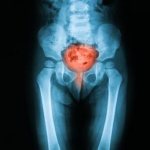

Почки, как часть эндокринной и мочевыводящей систем являются жизненно важными органами. Они не только обеспечивают вывод вредных веществ из организма, но так же контролируют водно-солевой обмен, регулируют артериальное давление и вырабатывают витамины и гормоны, необходимые другим органам.

Поэтому, заболевания почек приводят к серьезным нарушениям в функционировании всех систем организма. Изменения в почках, вызванные воспалительными или инфекционными процессами могут привести не только к почечной недостаточности, гидронефрозу, нефриту, аденоме простаты у мужчин и мастопатии у женщин, но также к гормональному дисбалансу и заболеваниям эндокринной системы.

С почками связан и мочевой пузырь. Если в почках камни, велика вероятность того, что в нем они тоже имеются. Поэтому предлагаемая система очищения рассчитана на то, чтобы изгнать камни из обоих органов.

Иглоукалывание является важной частью китайской медицины и широко используется во многих странах для лечения различных заболеваний, включая хронические болезни почек. Почки не только выполняют важную выделительную функцию, но и отвечают за выработку таких важных гормонов, как эритропоэтин, который стимулирует костный мозг, ренин, который регулирует кровяное давление и кальцитрол.